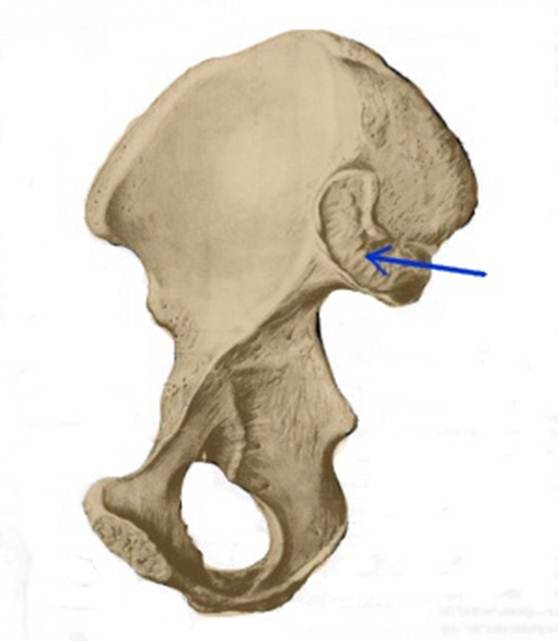

S:Стрелка указывает на spina iliaca posterior superior

S:Стрелка указывает на lambium internum

S: Стрелка указывает на spina iliaca posterior inferior

S: Стрелка указывает на tuber ischiadicum (латинский язык).

S: Стрелка указывает на incisura ischiadica minor

S: Стрелка указывает на incisura ischiadica major

S: Стрелка указывает на facies auricularis

S: Стрелка указывает на facies sacropelvica